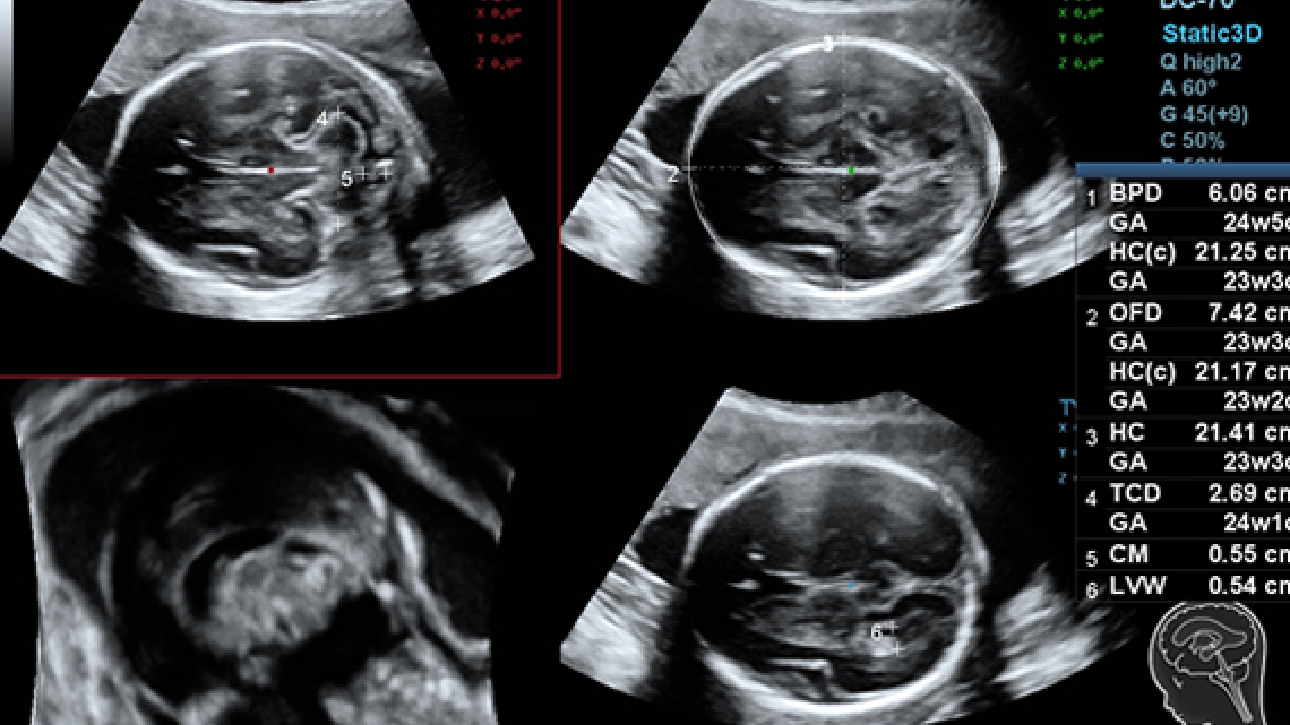

Imagens clĂnicas